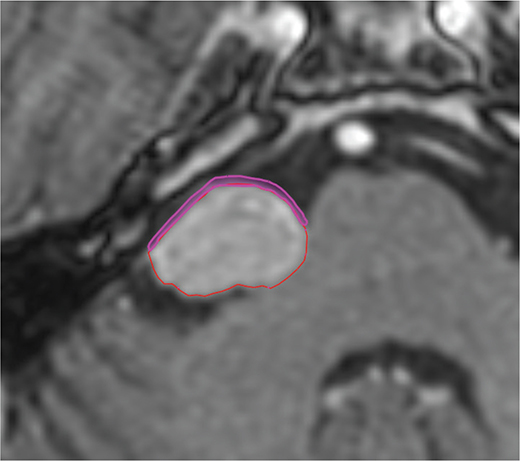

To achieve consistency in dose to OARs, all these structures were re-delineated as a part of this work by a senior physician in accordance with the latest guidelines [18, 19]. A crucial OAR in VS treatments is the facial nerve (VII) and this is usually difficult to visualize on MR images. However, it is located directly anterior to the target and therefore, a pseudo-volume was created consisting of a 1 mm slab anterior to the target in order to estimate the possible difference in doses to VII; see Figure 1 for an illustration. This pseudo-structure will be referenced to as ‘Anterior’ in the tables and data analysis. Since LGP does not have a function that would allow for a systematic creation of Anterior, the entire re-delineation was performed in an external software Eclipse 15.5. Thereafter the structure set was exported to MICE toolkit (Version 1.1.3, NONPI Medical, Umeå, Sweden) where a Boolean volume was created for each structure in the dimensions of the dose distributions. These Boolean volumes were then used in ReSamp to generate individual DVHs for the structures, for each dose distribution respectively. The generated DHV’s were compared to the exported DVH’s from LGP and Eclipse and the difference was found to be insignificant compared to the differences noticed by changing the algorithms, and since they also were systematic to all cases they were acceptable to use.

Figure 1. Shows the typical anterior 1 mm expansion we have used in our study as a pseudo-volume in order to estimate the possible differences in doses to the facial nerve.